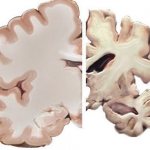

The second feature of the pathology is atrophy of the tissues of one of the cerebral hemispheres, due to which it is less supplied with blood and decreases in size.

Drying of one of the hemispheres due to Rasmussen's encephalitis is an irreversible consequence.

This atrophy of brain tissue has its own reasons, for example, increased apoptosis with a progressive decrease in the number of neurons.

When the cells of the gray and white matter of the brain (GM) are destroyed, the organ shrinks. The processes of atrophy begin in it (decreased vascular nutrition, decreased function). The disease affects one of the hemispheres. With necrosis of astrocytes (neuron cell processes), the connection between neurons is disrupted. The signal is not transmitted, so information from the outside world does not reach the person.

No other data on laboratory signs are revealed. CT and MRI scans show foci of brain inflammation in the early stages, and atrophy of one hemisphere in the later stages.